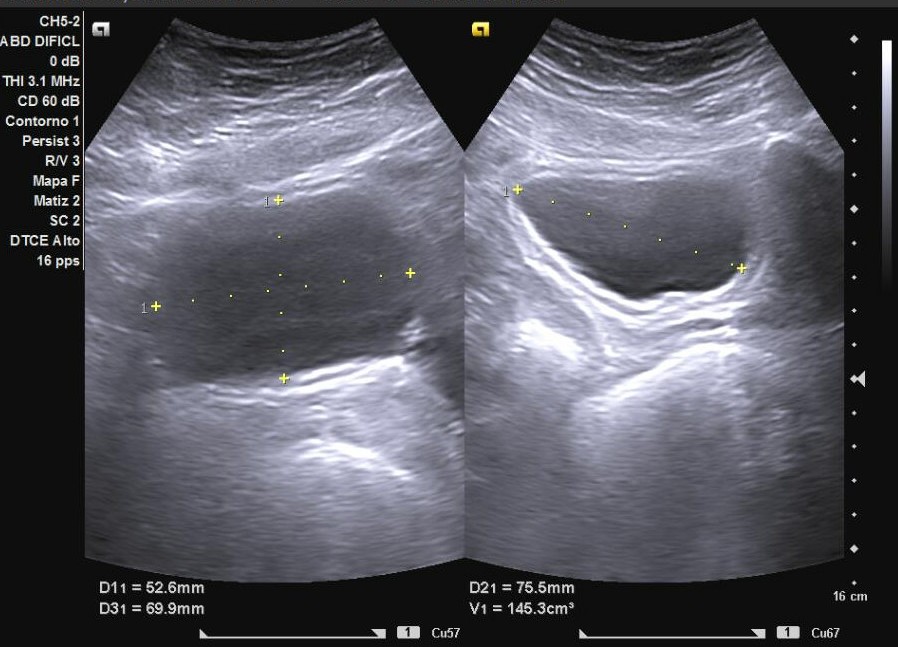

Hallazgos ecográficos

Esteatosis hepática grado I-II y además un divertículo vesical a nivel posterolateral izquierdo de 20 x 20 mm. Próstata de 22,6 cc, residuo posmiccional de 5,5 cc